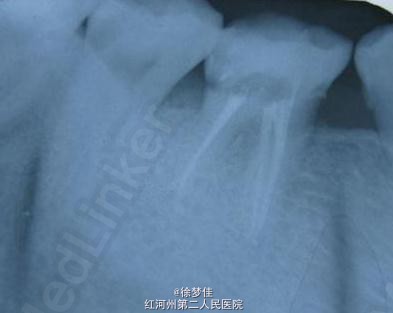

46牙的一次性根充

患者女性,35岁,牙疼求治。 主诉:右下后牙冷热疼一年多,近日加重,夜间疼,自发疼,疼痛呈放散性。 查:46远中邻面洞,冷(+++)探(+++)叩(-)不松。龈正常 诊断:46不可逆性牙髓炎 处:一次性根充。

查:46远中邻面洞,冷(+++)探(+++)叩(-)不松。龈正常

诊断:46不可逆性牙髓炎 处:一次性根充。

虽然操作难度大,但是,只要多练手,一次性根充还是可以的。